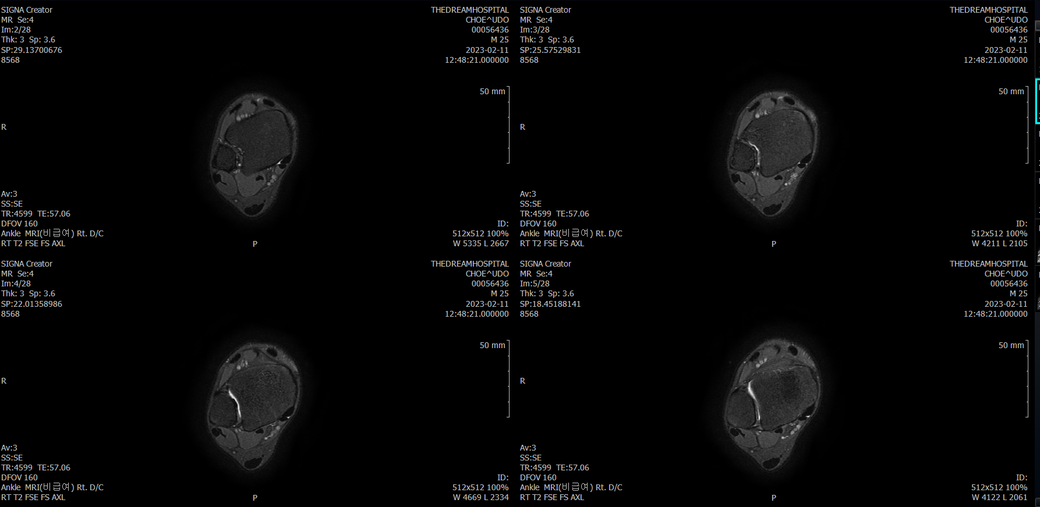

오른발목 mri 전체사진입니다. 제가 병원을 갈수없는상황인지라.... 봐주시면 감사하겠습니다.

엑스레이에서는 문제가 없다고 하여 오른발목 mri촬영했습니다.

우선 전반적으로 봤을 때 큰 이상은 없어보입니다.

전거비인대 등도 저명한 손상은 없는 것 같아 보이지만, 어느 부분의 통증 등으로 인해 촬영을 하셨는지 말씀을 해주신다면 보다 정확한 병변파악이 가능하겠으며, 병원에서 판독이 완료되신다면 전화 등으로 문의를 해보시는 것이 좋겠습니다.